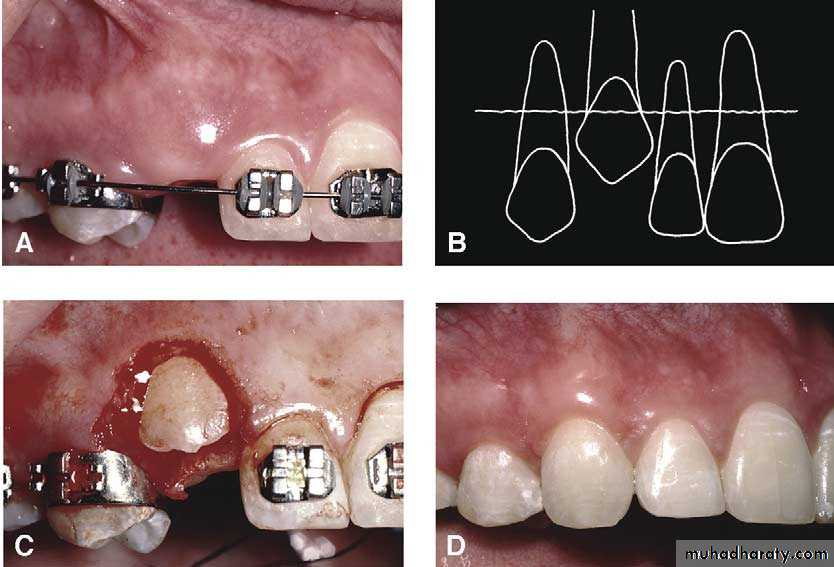

Surgical exposure

An attempt is made to assist the eruption of a malposed and unerupted canine into a functional position . It is considered when :1- there is adequate room in the arch to accommodate the tooth .

2- the potential path of eruption is unobstructed

3- exposure of the crown can be carried out as close as possible to the time at which normal eruption would occur .

The initial stage of the operation is to reflect the mucoperiosteum and to remove the bone overlying the tooth to expose the greatest coronal diameter, the incisal edge and the cingulum . before repositioning the palatal flap a window is excised in it corresponding to the bony cavity containing the crown .the flap is then sutured as usual and a pack of iodoform gauze should be pressed firmly in to the bony defect so as to cover the exposed crown .

Mosul university- College of dentistry-oral & maxillofacial surgery department

This pack should be held in position with suture and left insitu for 2-3 weeks to prevent granulation tissue and mucosa from overgrowing the denuded crown .after removal of the pack the progress of eruption should be observed at frequent intervals .

Following eruption of the tooth , orthodontic treatment may be required to guide it into a good position in the arch . Some times orthodontic traction is arranged at the time of surgery .